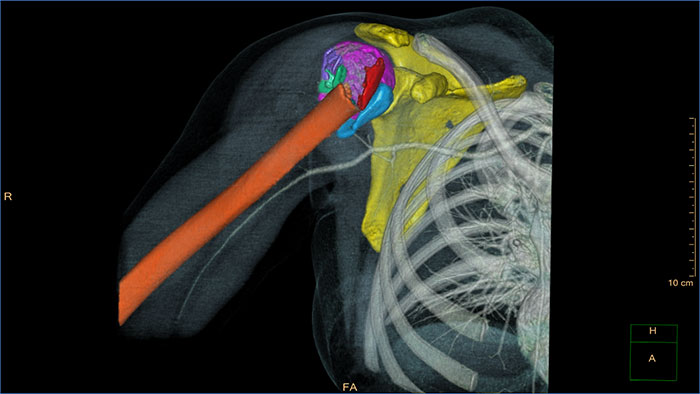

Due to an aging population as well as increases in obesity and sports activity, joint surgeries are on the rise. Perform a wide variety of tasks, such as assessment and reconstruction, thanks to the orthopedics application suite on IntelliSpace Portal. The tools are designed for even the most challenging musculoskeletal cases.

Take a closer look at cases involving bone and cartilage. CT Acute MultiFunctional Review, for example, includes an MSK and surgical planning stage. CT Bone Mineral Analysis, previously only available on Philips Extended Brilliance Workspace, helps you track and manage degenerative and metabolic bone diseases.

CT Acute MultiFunctional Review (AMFR) provides dedicated tools for findings detection, visualization and assessment of vessels, bones and spine anatomies in 2D and 3D CT images.